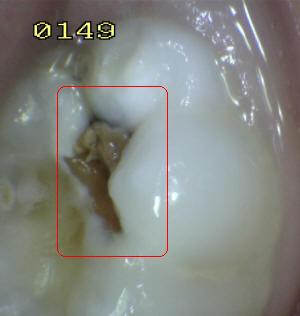

¿Determine los códigos pertinentes a cada imagen?

Click en el hipervínculo: Para comparar el resultado de su diagnóstico